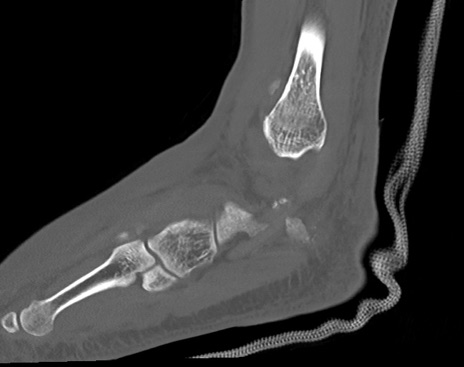

症例37 左足関節CT(矢状断像)

左足関節CT

冠状断像